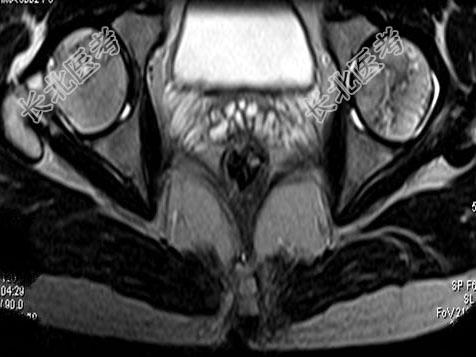

- 单项选择题男,24岁, 曾有外伤史,两侧髋部疼痛不适数月, 结合所提供的图像,最可能的诊断是 ( )

A、股骨头无菌性坏死

B、髋关节退行性变

C、未见异常

D、化脓性骨关节炎

E、类风湿关节炎两侧